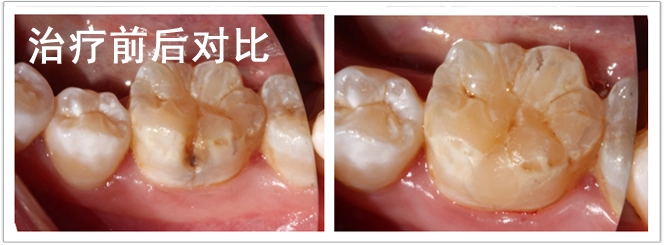

检查:颌面部未见异常,口内查:46颊面沟龋坏达牙本质层,温度测试正常。

诊断:46中龋

治疗计划:护充

治疗过程:46.去腐备洞 ,隔湿干燥,光照玻璃离子垫底,纳米充填, 调合,抛光。